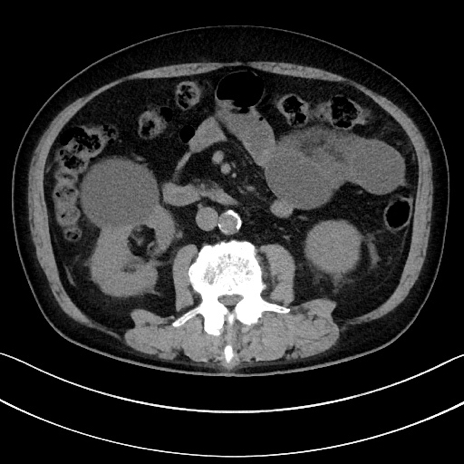

症例15(横断像)

【症例】70歳代男性

【主訴】腹痛

【現病歴】今朝から腹痛あり。全体的に痛い。特に左上の方。排ガスが今日はない。冷や汗が出る。

【既往歴】直腸癌術後

【身体所見】左側腹部〜上腹部に圧痛あり。腹膜刺激症状明らかなではない。軽度反跳痛。左下腹部に術後瘢痕あり。

【データ】WBC 7700、CRP 0.02